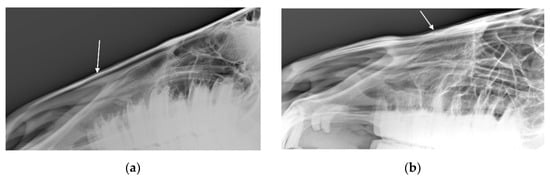

Percentage agreement between visual and palpation characterisations were 41% for Examiner 1 (unweighted κ = 0.269, z = 7.72, p < 0.001) and were 43.8% for Examiner 2 (unweighted κ = 0.310, z = 8.89, p < 0.001). The most common difference in rating between the visual and palpation modalities for Examiner 1 (27 horses) was from suspicious exostosis visually (see Figure 1a) to confirmed exostosis by palpation. The most common difference in rating between the modalities for Examiner 2 (12 horses) was from suspicious concavity (see Figure 1b) and confirmed exostosis visually to confirmed exostosis and concavity by palpation.

Figure 1. Photograph of profile of horse in which examiners (n = 2) agreed there was confirmed: (a) exostosis and (b) concavity in the nasal bones. Photographs courtesy of Missael García-Márquez.